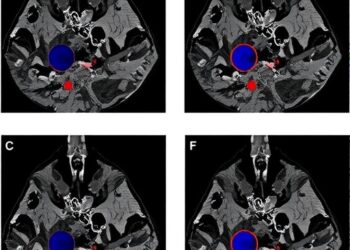

This study confirms the immune-boosting and hematopoietic-promoting effects of ribonucleic acid for injection II, which has a wide distribution of molecular weights and is rich in amino acids and nucleotides. Ribonucleic acid for injection II influences the gut microbiota and serum metabolites to enhance immunity in immunosuppressed mice induced by CTX, while also mitigating bone marrow injury and increasing hematopoietic cells through mediating macrophage M1 differentiation, thereby improving hematopoietic dysfunction in mice.

Yuan Li, Meng Teng and Siyu Li et al. Macrophage differentiation in enhancing hematopoietic function of ribonucleic acid for injection II via multi-omics analysis. Acta Materia Medica. 2024. Vol. 3(3):289-304. DOI: 10.15212/AMM-2024-0001